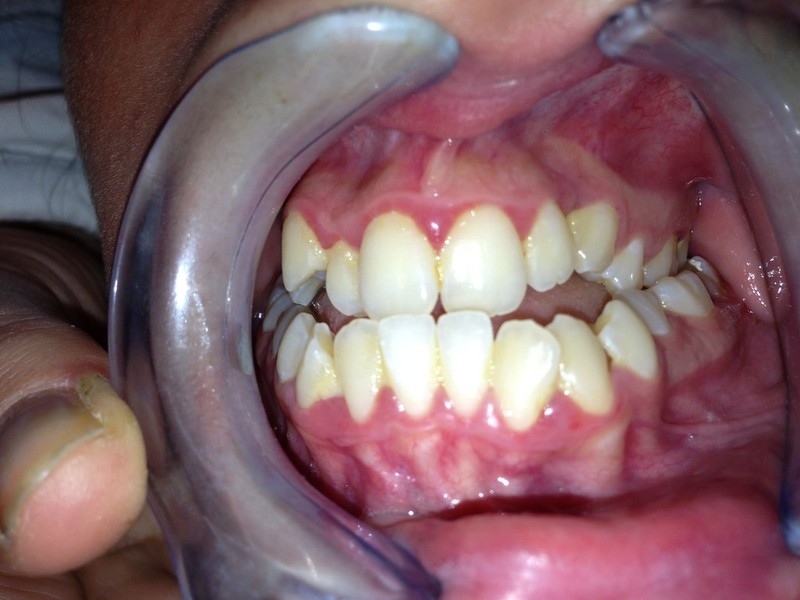

Paziente candidato a intervento di chirurgia Ortognatica

I risultati Arrivano e si vedono.

Uno dei nostri ultimi cambiamenti radicali.Il tuo sorriso può essere più vicino di quello che immagini